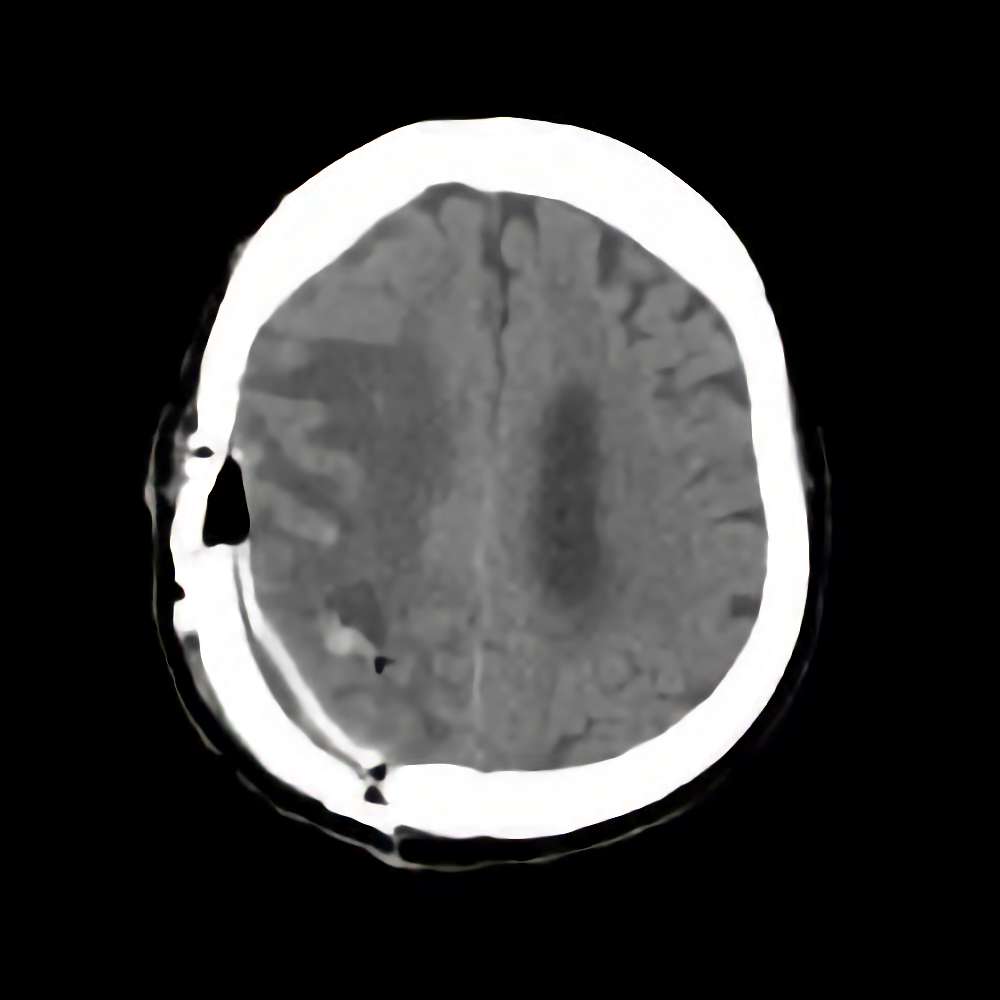

脳腫瘍

断層撮影

手術前1

No.’16_44 手術前1

No.’16_44 手術後